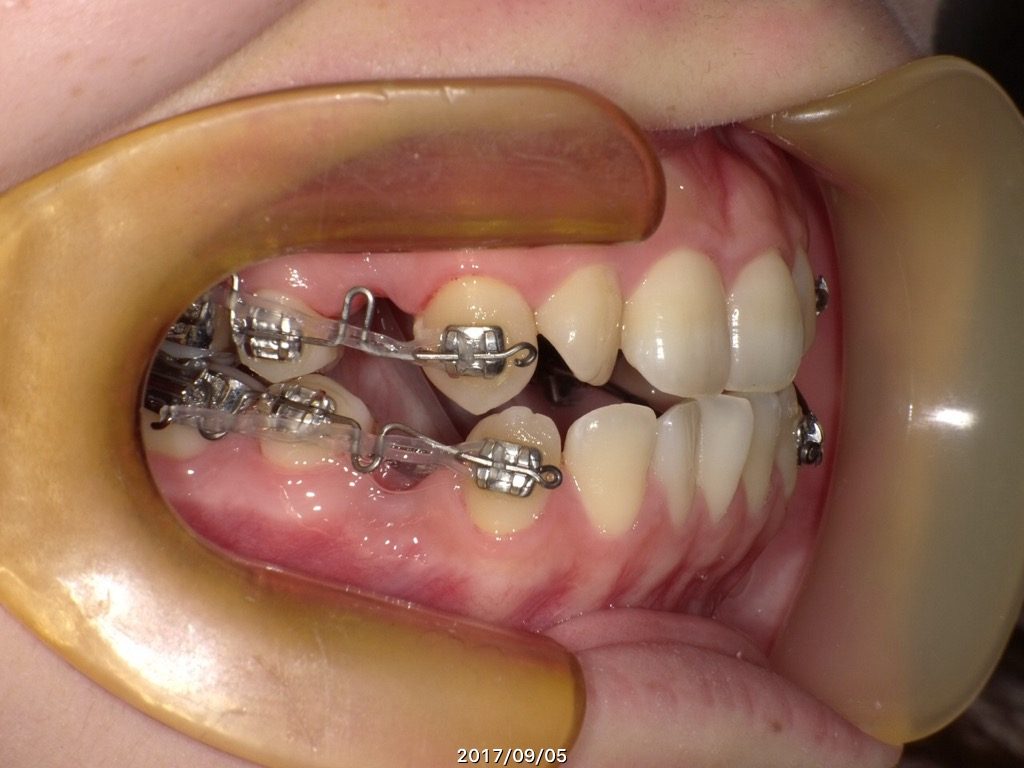

抜歯をする方は一時的に側面にブラケットを装着します。↓

↑なぜこのようにするかというと、、、、

とっても難しい話になってしまうので簡単に説明すると

・抜歯をしたスペースを早く埋めるため

抜歯したスペースを早く埋めないと骨の吸収が始まってしまうので、吸収を防ぐために行います。もちろんインビザラインでも抜歯した隙間を埋めることが出来ますが、マウスピースの使用時間が短かったりすると、思うように埋まらなく、歯の移動がしづらくなってしまいます。そのため、しっかりと力を加えて短期間で抜歯した間を埋めるためにこのような方法を当院では行っています☺

・フィットするマウスピースを作成するため

土台を整えるために固定式や取り外し式の装置をはじめに装着する方もいます。患者様によって診断結果や治療方針が異なるため、患者様皆様が同じ理由ではありませんが、歯と歯の間に隙間を開けるためや、噛み合わせを開放させる理由もあります。歯と歯が重なり合っていたりすると、完全にフィットするマウスピースの作成がとても難しく、「浮き」の原因になってしまいます。

↑上下4番目の歯を左右抜歯し、約半年間側面にブラケットを装着しました。